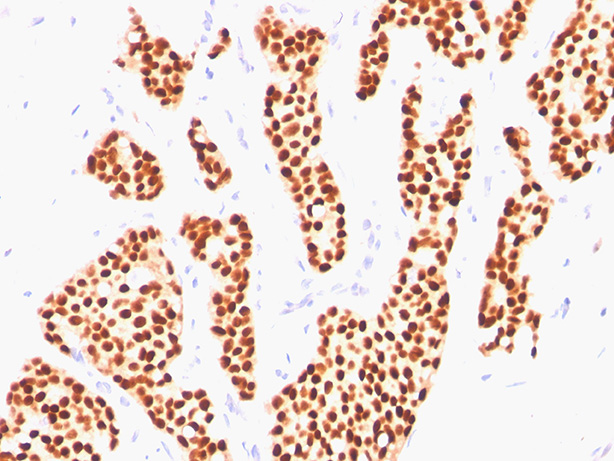

Formalin-fixed, paraffin-embedded human breast invasive carcinoma stained with Estrogen Receptor Ab (ER505).

This MAb is specific to ER alpha and shows minimal cross-reaction with other members of the family. ER is an important regulator of growth and differentiation in the mammary gland. Presence of ER in breast tumors indicates an increased likelihood of response to anti-estrogen (e.g. tamoxifen) therapy. This MAb is excellent for staining of formalin-fixed, paraffin-embedded breast carcinomas.